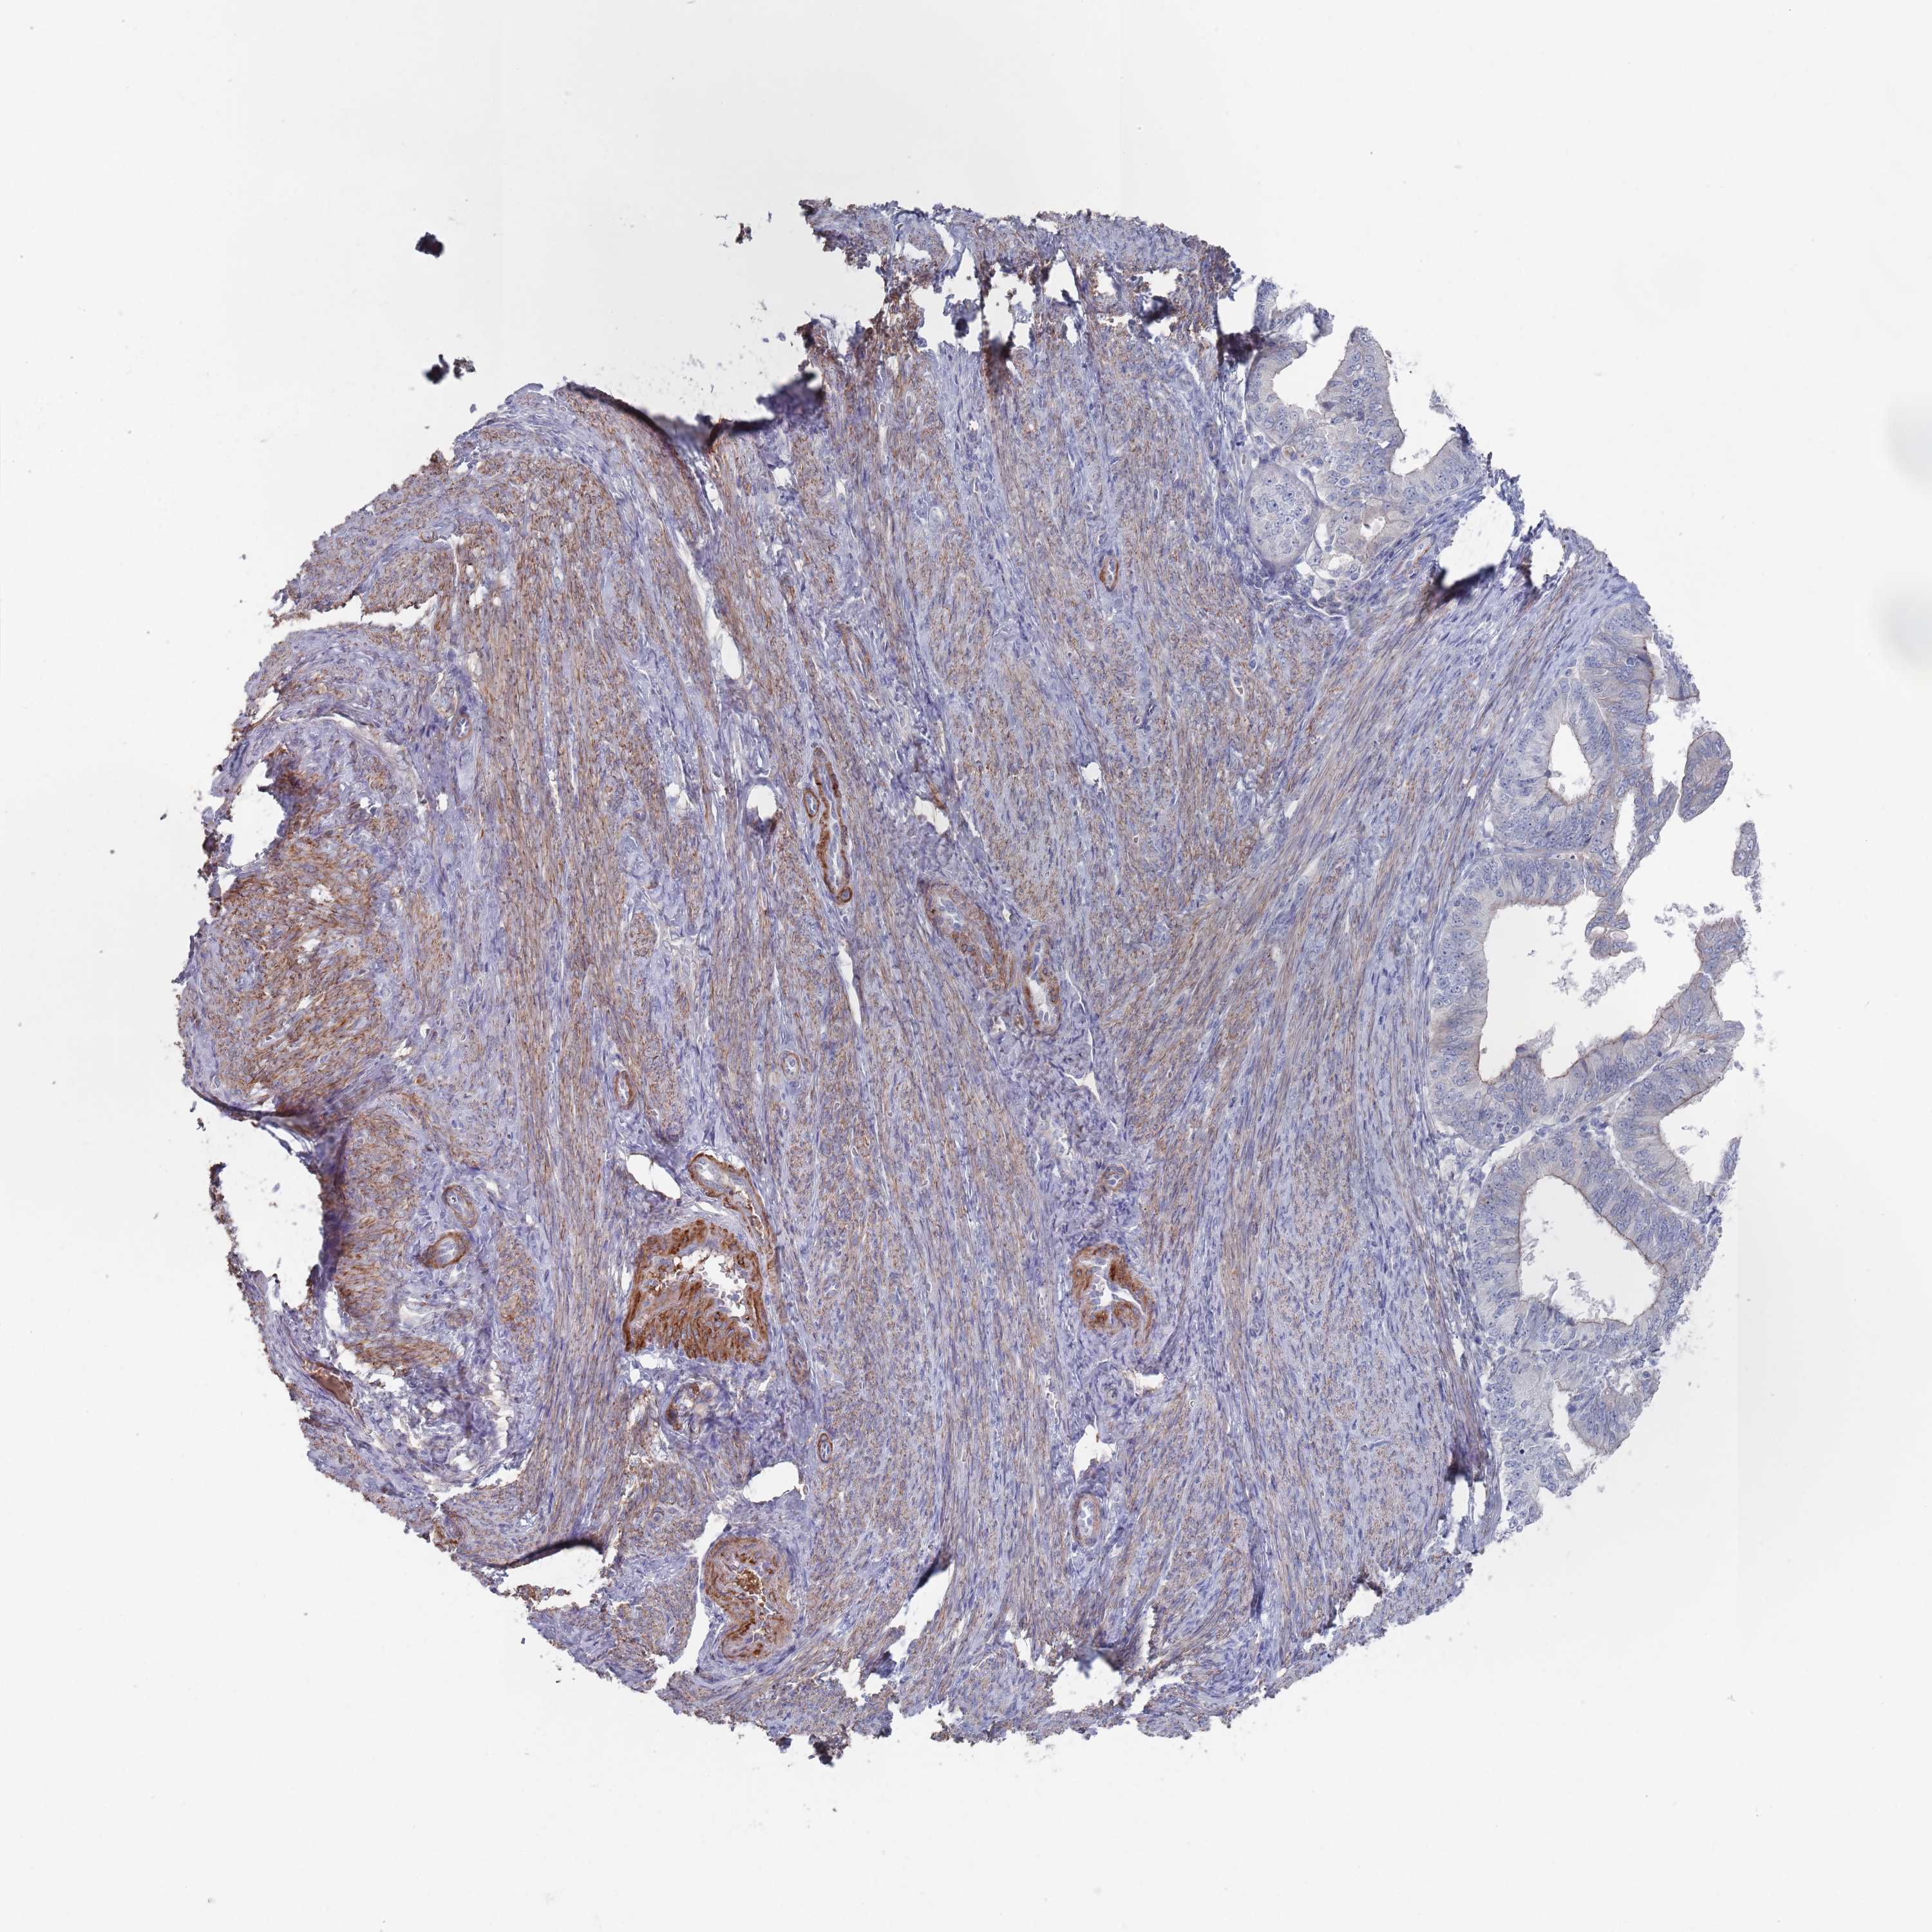

ENDOMETRIAL CANCER - Protein expressioni

A mouse-over function shows sample information and annotation data. Click on an image to view it in a full screen mode. Samples can be filtered based on level of antibody staining by selecting one or several of the following categories: high, medium, low and not detected. The assay and annotation is described here.

Note that samples used for immunohistochemistry by the Human Protein Atlas do not correspond to samples in the TCGA dataset.

Antibody stainingi

Antibody staining in the annotated cell types in the current human tissue is reported as not detected, low, medium, or high, based on conventional immunohistochemistry profiling in selected tissues. This score is based on the combination of the staining intensity and fraction of stained cells.

Each image is clickable and will lead to virtual microscopy that enables deeper exploration of all samples and also displays staining intensity scores, fraction scores and subcellular localization as well as patient and tissue information for each sample.

Antibody HPA042978

Antibody HPA048473

Staining

High

Medium

Low

Not detected

Intensity

Strong

Moderate

Weak

Negative

Quantity

>75%

75%-25%

<25%

None

Location

Nuclear

Cytoplasmic/membranous

Cytoplasmic/membranous,nuclear

Adenocarcinoma, NOS